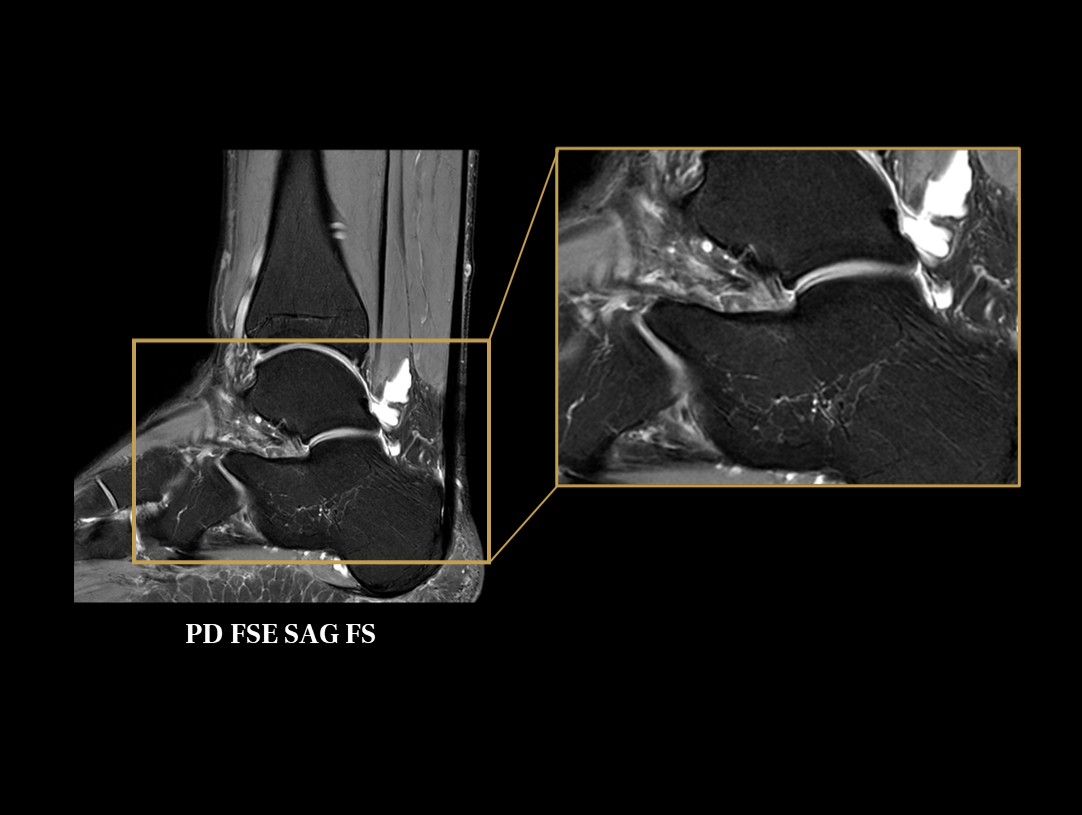

The 48 high-channel RF complements our integrated high-density coils, resulting insignificant image SNR increase.

The powerful 3.0T magnet uses a 170 cm short-magnet design to ensure high homogeneity of the magnetic field, which provides a solid foundation for fast imaging and excellent fat saturation over a large FOV, as well as outstanding off-center imaging.